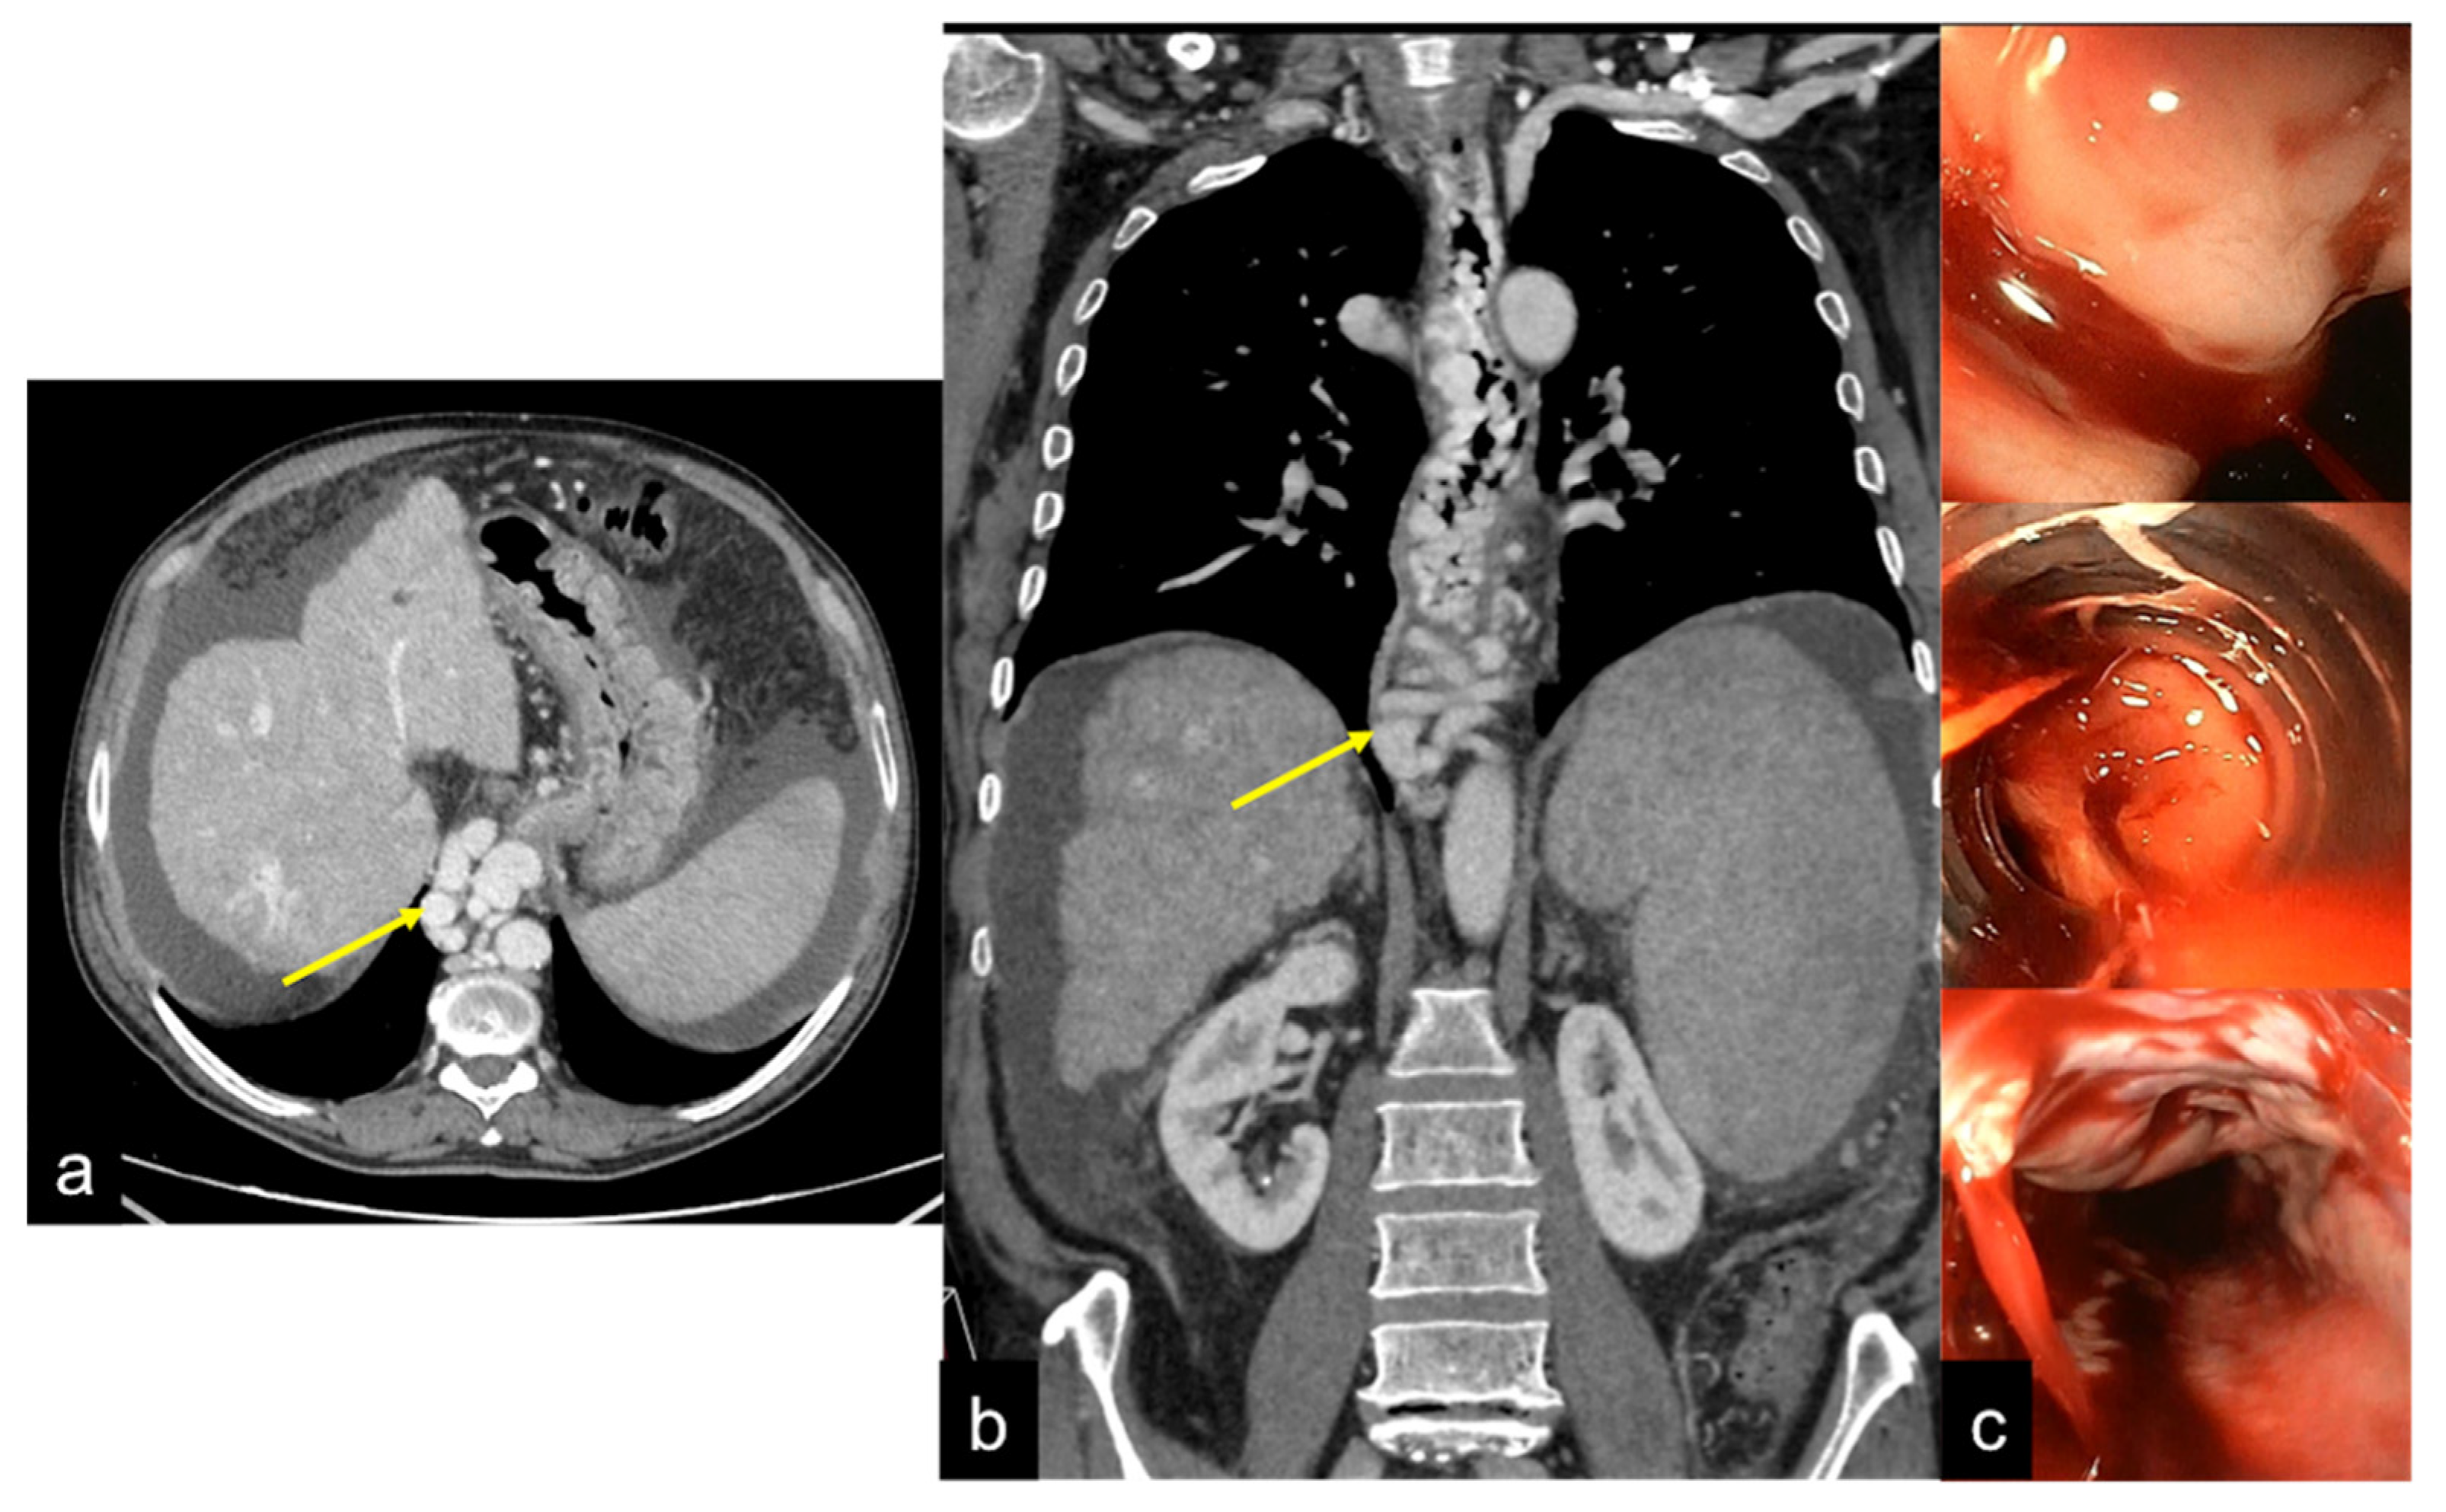

| Aorto-Gastric Fistula (Figure 28) | Copious bleeding. | A connection between the aorta and the gastric lumen. Absence of adipose cleavage planes. |

- Martino, A.; Bennato, R.; Oliva, G.; Pontarelli, A.; Picascia, D.; Romano, L.; Lombardi, G. Primary aortogastric fistula: An extraordinary rare endoscopic finding in the setting of upper gastrointestinal bleeding. Endoscopy 2021, 53, E60–E61. [Google Scholar] [CrossRef]